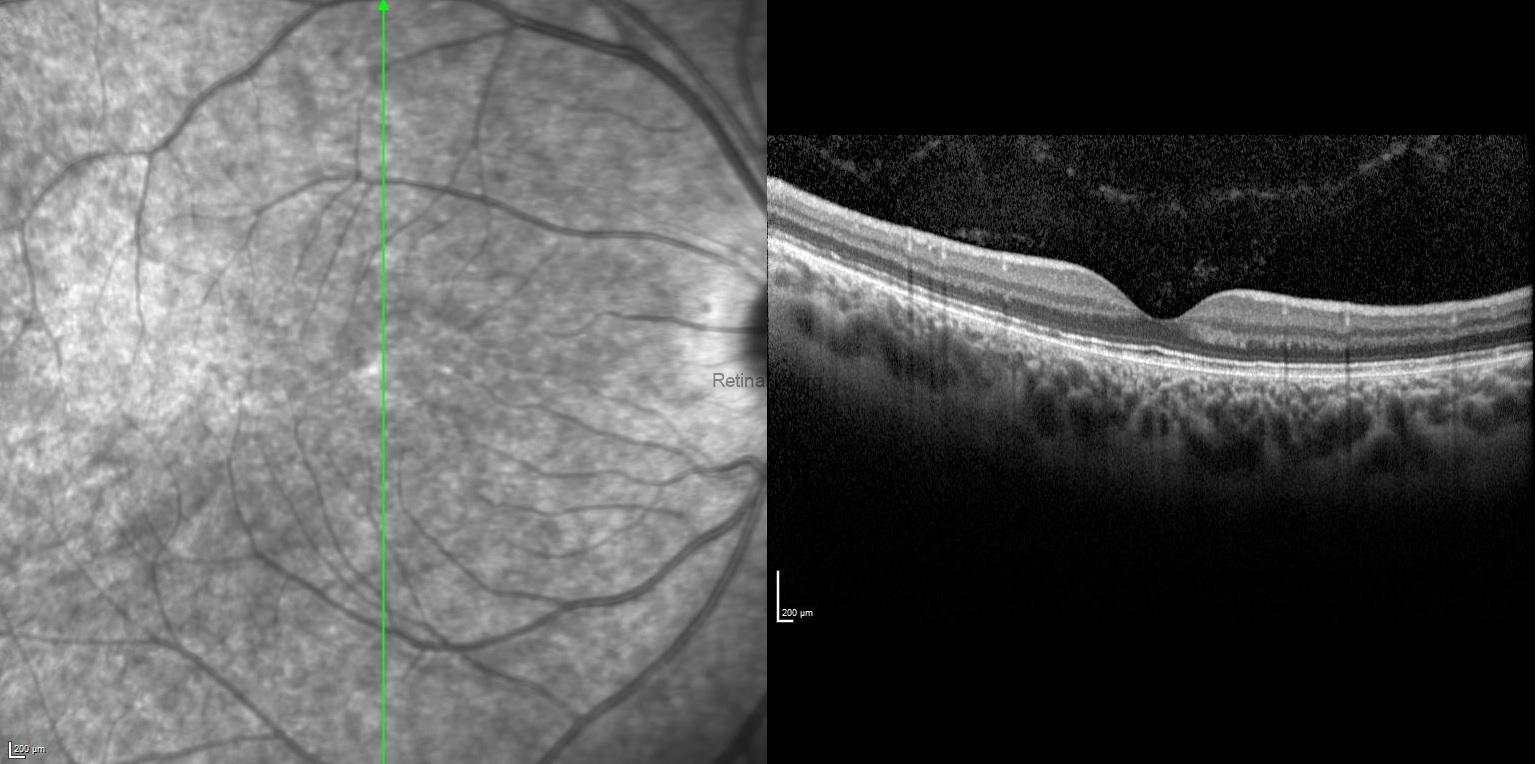

SD-OCT of the right eye showed attenuated inner segment–outer segment junction, absent upward displacement of subfoveal ellipsoid zone band, and mottled retinal pigment epithelium, while it revealed thickened and elevated retinal layers at the macula due to the subretinal and intraretinal fluid with foveal and extrafoveal protruding hyper-reflective material in the left eye.